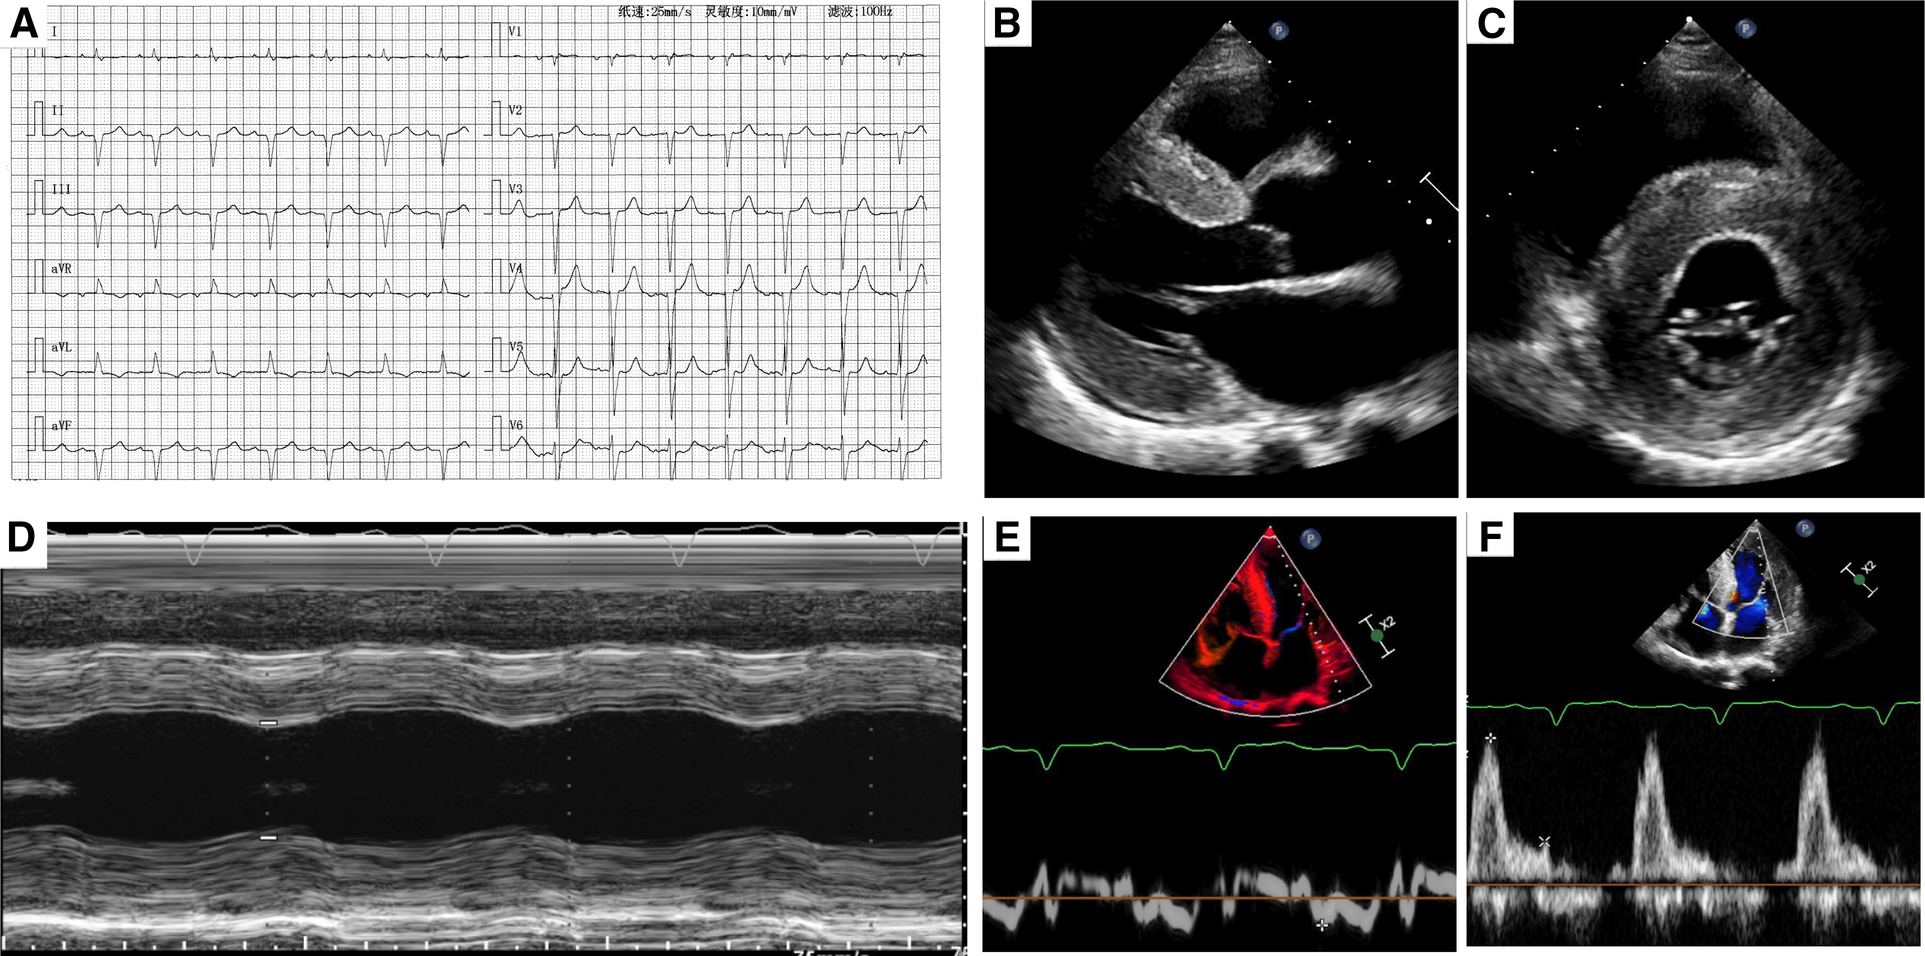

ECG showed old inferior and interior wall myocardial infarction (Figure 1A). For laboratory testing, NT-proBNP was found significantly increased at 4,050.0 pg/ml (threshold value, 125 pg/ml). Complete blood count, myocardial enzymes, and biochemical examination were normal.

Figure 1

(A) A typical electrocardiogram. (B,C) Two-dimensional transthoracic echocardiography showed left ventricular hypertrophy and myocardium speckled pattern. (D) The contractility function was reduced. (E,F) Diastolic dysfunction (stage III) was found by pulse-waved Dopper echocardiogram.

Transthoracic echocardiography demonstrated diffuse hypertrophy of the left ventricular wall and “ground-glass” enhancement of myocardial echogenicity. The thickness for basal, middle, and apical segments of the interventricular septum was 24, 22, and 21 mm, respectively. The corresponding thickness of the segments for the inferior wall was 24, 18, and 22 mm, respectively. In addition, the contractility function was reduced with an estimated LVEF of 43%. The right ventricular wall motion was normal with a right ventricular fractional area change of 38%. Furthermore, bi-atrial enlargement and diastolic dysfunction (stage III) were observed. What's more, mild to moderate insufficiency was found in the aortic, mitral, and tricuspid valves (Figures 1B–E).